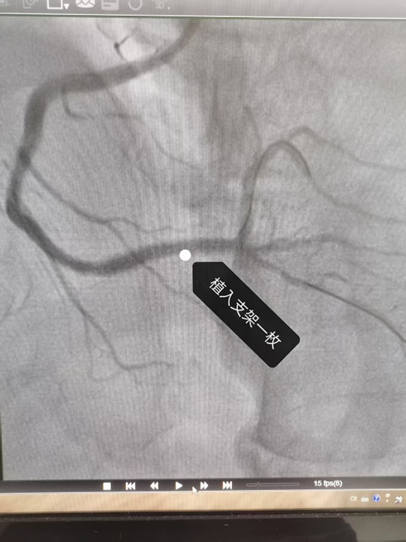

经过紧张抢救,手术团队成功为李先生实施了冠状动脉介入手术,疏通了完全堵死的右冠脉,并植入支架。目前,李先生恢复良好,生命体征平稳。

△堵住患者右冠脉的血栓